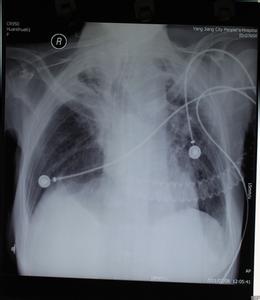

新生儿肺炎是新生儿期的常见病,较为严重的则是重症肺炎,是呼吸道感染而引起的炎症,发病率高、死亡率也较高。该炎症以弥温性肺部病变及不典型的临床表现为其特点,需及早诊断和正确处理。孕妇如果在产前曾经发生过感染性疾病或胎儿曾发生过宫内窘迫的话,出生之后新生儿要警惕有产前感染性肺炎的可能。

大多数新生儿肺炎是生后感染引起的,称晚发型肺炎,主要是家庭中与新生儿密切接触的成员感冒或呼吸道感染后通过飞沫传播给新生儿的。出生后肺炎诊断有赖于患儿的症状和体征,诊断虽较容易,但要注意病情的发展和并发症。如果不及时治疗会引起呼吸窘迫、甚至窒息,严重者会因为缺氧引起大脑损伤,留下永久的后遗症(如癫痫)。